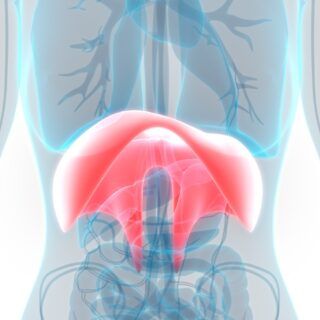

Bei der Leber (Hepar) handelt es sich um die größte Drüse im menschlichen Körper. Die rotbraune Drüse erreicht ein Gewicht von 1,4 bis 2 kg. Im rechten Oberbauch wird sie von den unteren Rippen geschützt. Anatomisch gliedert sich das Organ in einen linken und einen rechten Leberlappen, wobei der linke Lappen wesentlich größer ist. Die Leber ist mit mehreren Bändern in der Bauchhöhle verankert. Unten an der Leber befindet sich die Leberpforte (Porta hepatis). Hier treten Blutgefäße, Nervenfasern, Gallengänge und Lymphgefäße in das Organ ein. Im Inneren zeigt sich die Leber als mehrlappiges System, welches wiederum aus vielen kleinen Leberläppchen und Leberzellen (Hepatozyten) besteht.

Die Leberarterie und die Pfortader, welche sich an der Unterseite der Leber befinden, treten über die Leberpforte in das Organ ein. Über die Leberarterie fließt sauerstoffreiches Blut in die Leber. Zeitgleich fließt über die Pfortader sauerstoffarmes Blut in die Leber. Bei der Pfortader handelt es sich um eine Vene, die das Blut aus dem Bauchraum (Milz, Bauchspeicheldrüse, Magen, Darm, Gallenblase) in die Leber leitet. In der Folge gelangen so verschiedenste Stoffe in die Leberzellen. Hierzu zählen unter anderem Einfachzucker und Aminosäuren. Nun entscheidet die Leber je nach Bedarf und Qualität, welche Stoffe direkt benötigt, gespeichert oder umgewandelt werden. Nicht umsonst ist die das Organ unter dem Namen „Chemiewerk“ bekannt.

Die Leber ist eng mit der Gallenblase verknüpft und die Zusammenarbeit ist für unsere Verdauung und Vitaminverwertung von großer Bedeutung. Aus der anatomischen Perspektive befindet sich die Gallenblase unter dem Organ in einer kleinen Einbuchtung und ist über einen Gallengang direkt mit ihr verbunden. Pro Tag stellt die Leber in etwa 600 ml bis 1.000 ml Gallenflüssigkeit her. Die Gallenblasse speichert das gelb-bräunliche Sekret und verdickt dieses. Bei der Verdauung von fettreichem Essen gibt die Gallenblase die Gallenflüssigkeit an den Darm und Zwölffingerdarm ab. Hier werden wiederum Fette aus der Nahrung gespalten und verarbeitet.